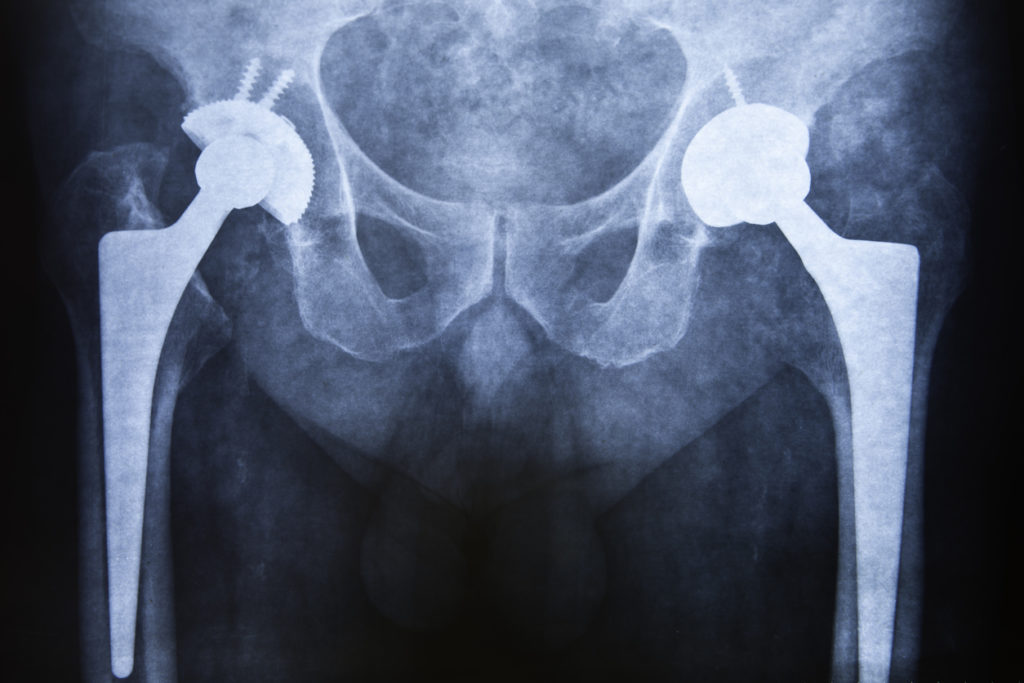

During the procedure, the orthopedic surgeon makes an incision, either in the front or at the side (or back), depending on the approach being used. Once the doctor accesses the hip, they will remove the damaged cartilage and bone and replace it with a prosthesis made of metal and plastic. The surgeon will be very careful to keep healthy tissue and bone intact.

The metal part replaces the femoral head (which is attached to a stem that is fitted into your thigh bone), while the plastic-lined metal shell replaces the socket part of the hip joint. The socket component has a porous surface, which allows for bone ingrowth. The doctor may use a special type of cement to attach the prosthesis to the bone. The cement and eventual bone ingrowth will hold the prosthesis in place.